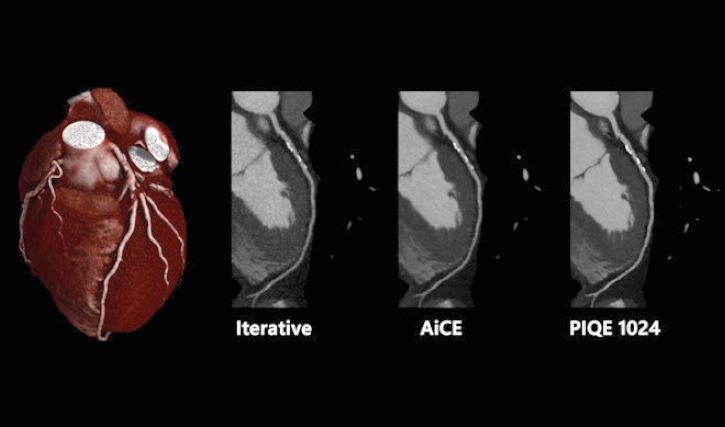

але без збільшення дози опромінення», – сказав він. «Загалом реконструкція глибокого навчання була дуже добре сприйнята нашими радіологами. Aquilion ONE / INSIGHT Edition використовує два типи DLR, один із яких Advanced intelligent Clear-IQ Engine (AiCE), який ми зазвичай

використовуємо при скануванні тіла, і Precise IQ Engine (PIQE), який ми зазвичай використовуємо, на даний, момент для коронарних артерій, але також доступний для обстеження

тіла».

«Перевага PIQE 1024 полягає в тому, що він дає нам набагато вищу просторову роздільну здатність без збільшення дози радіації. Оскільки це покращує просторову роздільну здатність, ми можемо отримати зображення коронарних артерій з кальцинатами та стентами зі зменшенням артефактів від них. Ми працюємо на цьому апараті всього 5 тижнів, але ми набагато впевненіші в діагнозі, оскільки роздільна здатність набагато вища», – додав він.

CTA серця з різними алгоритмами реконструкції лівої передньої низхідної артерії, що показує підвищену просторову роздільну здатність за допомогою PIQE 1024.

Precise IQ Engine (PIQE)

Це алгоритм реконструкції

глибокого навчання, який

максимізує власну роздільну

здатність комп’ютерної

томографії для отримання

матричних зображень

суперроздільності 1024.

Зображення PIQE показують

чіткіші анатомічні деталі

для кращого окреслення

невеликих анатомічних

структур для більш точного

діагнозу.